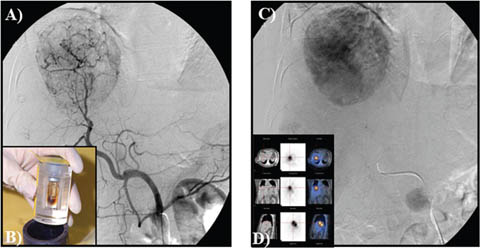

TACE is currently the standard of care for patients with intermediate–stage HCC with preserved liver function (7880). TACE is useful for patients that have a Child-Pugh score A or B with tumor diameter of >4 cm or four or more tumors as well as those with single tumor in which it is challenging to carry out liver resection or locoregional therapies as a result of systemic co-morbidities or anatomical limitations (81). TACE takes advantages of the dual arterial and portal venous liver parenchymal blood supply with preferential arterialization not only in cirrhotic liver but of HCC. It involves the selective arterial embolization with a gelatin mixed with lipiodol (a radiopaque contrast agent) with or without chemotherapy (doxorubicin, cisplatin or mitomycin C), into the tumor’s feeding blood vessel (66). The blockage of the arteries supplying the tumor results in tissue necrosis (Figure 10) (68, 79). In practice, TACE is a recommended therapy for patients with unresectable HCC, nonvascular invasion or disease outside the liver (64). TACE can also be used with drug-eluting beads (DEB-TACE) and evidence exists that patients who are on DEB-TACE treatments for unresectable HCC have better performance in comparison to those on conventional TACE (66). In addition, TACE is being used for the downstaging of tumors in association with systemic therapy or as bridge for transplantation.

Fig 10

Figure 10. Trans-arterial chemoembolization of the liver for hepatocellular carcinoma. A and B. Selective arterial embolization of the vessels feeding the tumor in the liver. C. Tumor visualized by CT scan. The procedure is performed with or without chemotherapy. D and E. After embolization, angiography showed obliteration of feeding vessels with shrinkage of the tumor. F. Follow up CT scan after embolization. Note an increase in patient’s ascites.